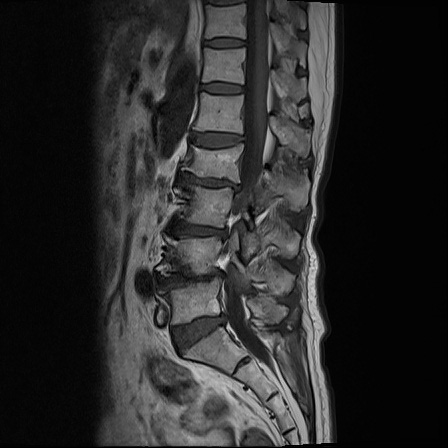

Ӵϲ ɿ ô ô 㸮 ٸ ̾ϴ. ϵ Ͻð ܻ 㸮 20⵿ ͽϴ. mri ˻ ɿ Ȳ ʹ ؼ Ȳ̶ ߽ϴ. ϻȰ ϰ 鼭 ½ϴ. ̴ ø鼭 Ͻô Ȳ ̷ ġ ص ȸ ϴ. δ Ҵµ, ù ȸԲ ˷ֽ ϰ β ϰ, ˷ֽ ü ƮĪ ϸ鼭 ȭǸ鼭 Ӵϲ ȸų ְ ǰ, β 鼭 ʴ β ؾϴ ŷο 1ϸ ijħ ڸ ǥ Ʈ ߽ϴ. ȸ ȭϽø鼭 Ϸ簡 ٸ ȸǽð 4ְ Ǿ Ǯ鼭 ¦ ҽϴ. ħ ȸ ȭϸ鼭 ڼ ü ƮĪ ϴ. ȥڼ Ͻʴϴ. ٳø鼭 ó Ͻ ʴϴ. ̾ ְ ̳ ߵ ʰ ϴ ȸԲ Ͻʴϴ. ʹ ϸ鼭 ϴ. Ȩ - ϱ ٴ Ȳ MRIԴϴ. |